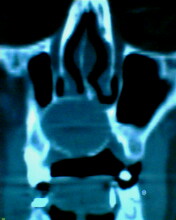

患者:男71岁,右侧上颚肿物无痛性生长7年.

右上颌骨近中线部见类圆形低密度区,上方见一液平,周围见一薄硬化环,前下方见一牙根,后方累及水平板。上方突入鼻腔前下部,下方突入口腔。

考虑:右侧上颌骨囊肿伴感染。